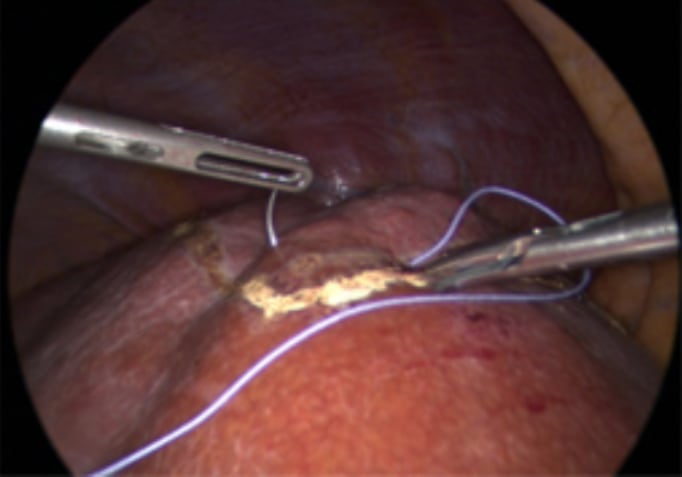

Picture showing large tear in right hepatic vein. The patient was positioned in semiprone. CVP during parenchymal transection was 8. Although CVP was relatively high, blood loss was minimal giving the surgeon time to suture the venous tear.